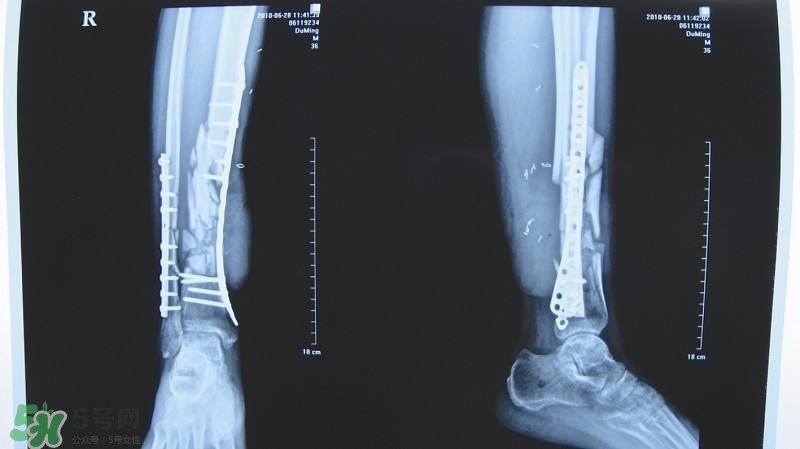

1、X線照片顯示骨折線模糊,有連續(xù)性骨痂通過(guò)骨折線;